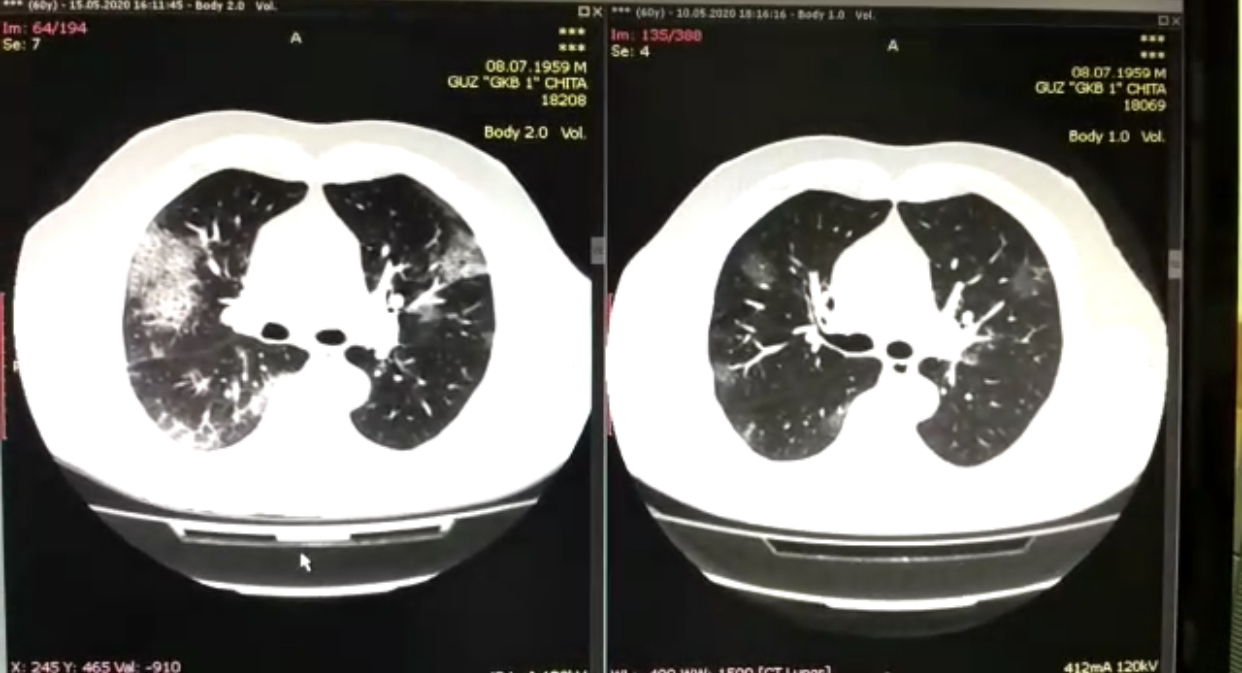

Часть вторая: очаги за несколько дней расползаются до тотальных размеров «Мужчина 60 лет поступает в моностационар. Самочувствие его вполне удовлетворительное. Из симптомов – кашель, высокая температура. Компьютерная томограмма показала начальные признаки поражения лёгких. Мы внимательно наблюдаем за пациентом. Назначаем лечение. Ежедневно оцениваем его состояние. Но на 5-ый день, несмотря на проводимую терапию, еле видимые участки "расползлись" до больших размеров и лёгкие тотально поражены», - рассказывает доктор.

На фото изображены легкие пациента. Слева - белые очаги, поразившие легкие. На снимке справа – его же легкие ещё пять дней назад, где просматривались лишь небольшие поражения.

Заключение о представленном клиническом случае: пациент жив, состояние тяжелое.